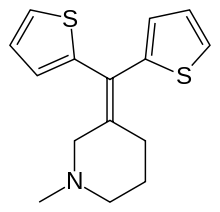

Thiambutenes

Structures